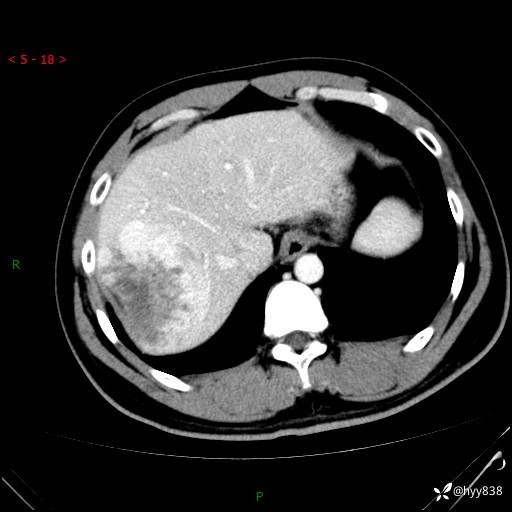

患者性别:男

患者年龄:29岁

简要病史:外院超声提示肝脏占位性病变

辅助检查:CT

临床诊断:肝占位

增强动脉期

原发性肝癌 (50)